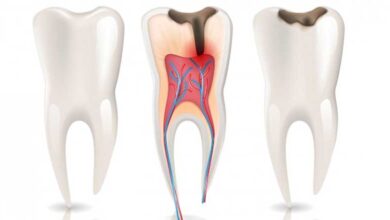

آیا عصب کشی ممکن است باعث عفونت شود؟

آیا عصبکشی ممکن است باعث عفونت شود؟ بله، اگرچه درمان ریشه (عصبکشی) یک فرایند درمانی بسیار موفق با هدف اصلی حذف عفونت و بافتهای آسیبدیده از داخل دندان است، اما خود این درمان نیز میتواند در درصد کمی از موارد به دلیل پیچیدگیهای بیولوژیک و فنی، منجر به عفونت ثانویه یا باقی ماندن عفونت اولیه گردد. درک این ریسکها به…

آیا عصب کشی دندان همیشه موفقیت آمیز است؟

آیا عصبکشی دندان همیشه موفقیتآمیز است؟ درمان ریشه (عصبکشی) یکی از پیشرفتهترین و قابلاعتمادترین روشهای درمانی برای حفظ دندانهای آسیبدیده است. با این حال، موفقیت آن هرگز صددرصد تضمینشده نیست. در حالی که میزان موفقیت کوتاهمدت آن بسیار بالا (حدود ۸۵ تا ۹۷ درصد) است، عوامل متعددی میتوانند در بلندمدت شانس شکست درمان را افزایش دهند. درک این عوامل برای…

آیا عصب کشی دندان نیاز به جراحی دارد؟

آیا عصبکشی دندان نیاز به جراحی دارد؟ عصبکشی (درمان ریشه یا اندودنتیکس) در حالت استاندارد یک روش درمانی غیرجراحی و رایج برای نجات دندان است. در این درمان، دندانپزشک از طریق تاج دندان به کانالهای ریشه دسترسی پیدا میکند و نیازی به برش لثه یا استخوان ندارد. جراحی ریشه که معمولاً به شکل آپیکواکتومی (Apicoectomy) انجام میشود، یک درمان تخصصی…